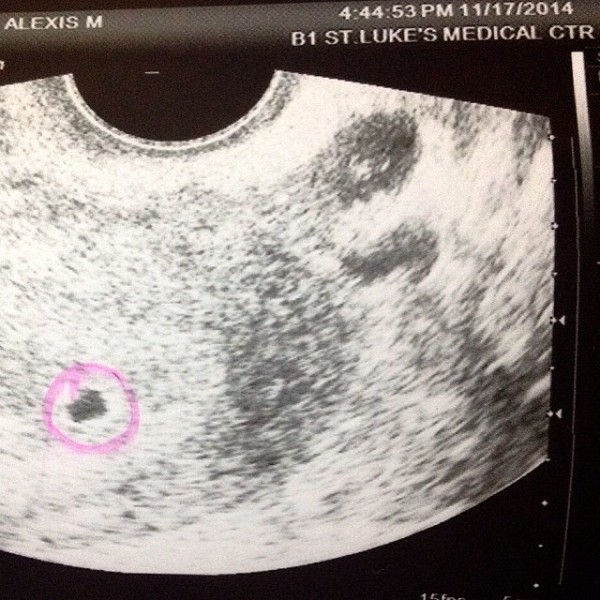

Last Sunday, Nov. 23, she posted on Instagram proof that they’re expecting, and shared that she is five weeks pregnant. She also asked for prayers “for my bleeding to stop” and that “maging makapit si baby.”